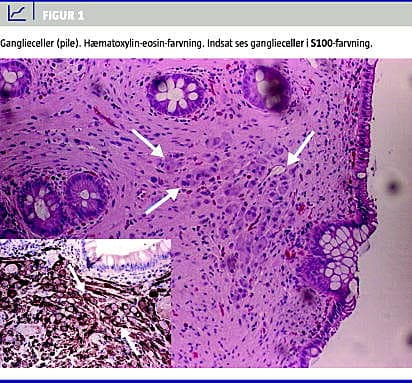

Ved koloskopi fandt man en lille polyp ca. 20 cm fra anus. Tarmen var herudover fuldstændig upåfaldende. Ved mikroskopi sås en polypøs slimhinde med uensartede krypter, enkelte let dilaterede, beliggende i et fint fibrillært stroma, der indeholdt adskillige ganglieceller, især superficielt. På nogle vævsflager var der komplet tab af krypterne, andre steder sås der spredtliggende krypter. Der var ingen epiteldysplasi. Ved immunhistokemisk undersøgelse sås det som ventet, at gangliecellerne i lamina propria var positive ved S100-farvning (Figur 1 ).